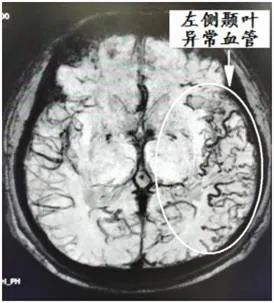

患者白某,男,68岁,汉族,因“突发言语不清5小时”于2021年1月28日 16:37以“急性脑血管病”就诊于我院急诊科。急诊完善颅脑CT未见出血,考虑急性脑梗死,由于错过了静脉溶栓治疗时间窗,准备于导管室取栓治疗,但完善脑血管造影后发现患者并非急性脑栓塞病变,而是硬脑膜动静脉瘘所致。因此为求诊疗精确,于内科保守治疗一周,并远程邀请兰大二院神经外科介入专家张海林教授会诊后确诊为硬脑膜动静脉瘘,并决定于今日行介入下颅脑动静脉瘘栓塞术。

脑病介入科曹骅主任、赵宏廷主治医师先进行左侧颈外动脉血管造影,以明确复杂瘘口,术前造影:颈外动脉中包括枕动脉、耳后动脉、颞浅动脉的多个分支通过硬脑膜向颅内静脉形成异常引流,栓塞术难道很大。